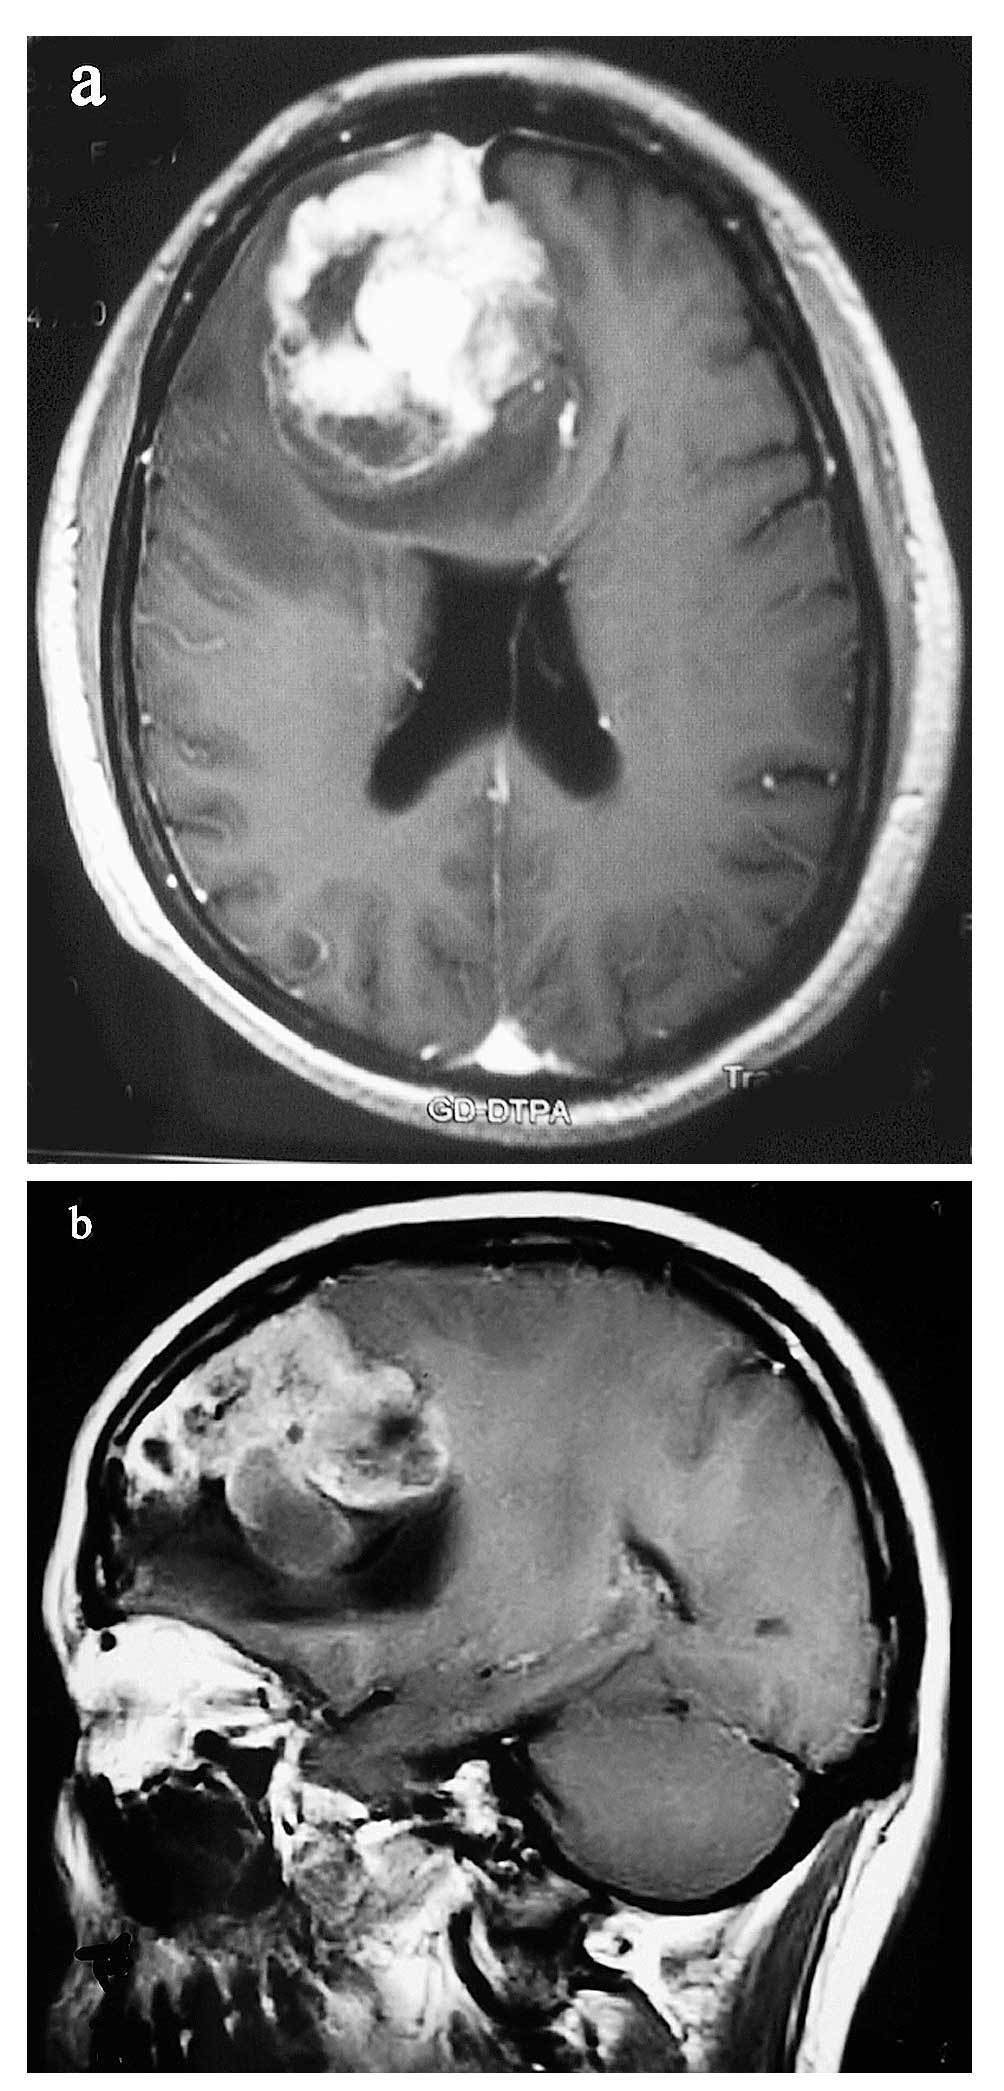

deficits or changes in mental status (38). Aside from symptoms and signs, the

best imaging diagnostic method is a T1-weighted gadolinium-enhanced

MRI, particularly the three-planar images (Fig. 1A and B) and diffusion tensor

imaging. Radiologically, GBMs present with irregular contours and a

peripheral zone with strong contrast enhancement around a darker,

hypodense, necrotic area and with the non-enhancing tumor extending

outside the area of enhancement (39). Magnetic resonance spectroscopy